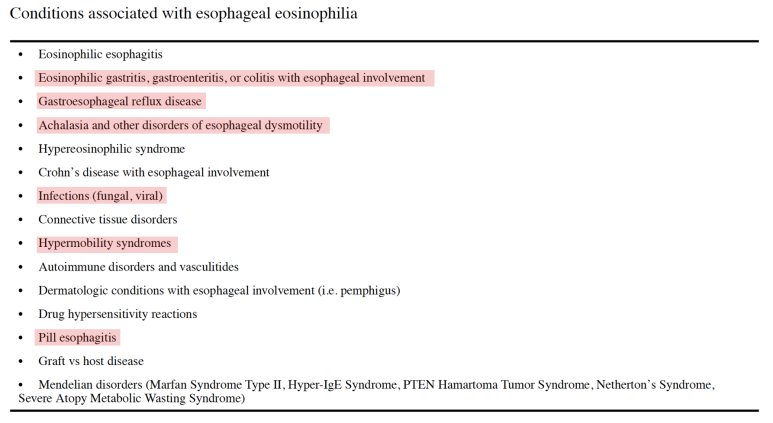

조직검사는 유럽의 경우 6개소를 시행할 것을 권고하고, 미국의 경우 2-4개의 promixal, distalesophagus에서 시행할 것을 권고하고 있습니다.진단 기준 상의 내용을 종합하여 호산구 식도염의 진단 기준을 확인하게 됩니다.먼저 전 세계에서 모여 만든 AGREE 컨퍼런스에서는 식도의 Dysfunction이 발생하는데 아토피 소인이 있고 내시경적으로 특징적인 소견이 있으며 조직학적으로 HPF당 15개의 호산구가 확인되어야 합니다. 이때 중요한 것은 호산구의 침착이 식도에만 국한되어야 하며 다른 2차적인 원인에 의해 식도 내 호산구가 증가하지 않는 것입니다. 즉, 다른 질환 없이 식도로만 호산구가 증가한다는 것을 의미합니다.

예를 들어 Achalaisa, 약물유발성식도염, 감염, GERD에 의해서도 호산구가 증가할 수 있으나 이러한 질환이 함께 발생할 경우에는 호산구식도염으로 진단할 수 없습니다.

즉, 식도 관련 증상이 있을 경우 내시경을 실시하고 조직검사에서 HPF당 15개 이상의 호산구가 있을 경우 식도 내에 호산구를 증가시키는 질환이 모두 제거된다는 가정 하에 호산구 식도염이라는 진단명을 붙일 수 있습니다.